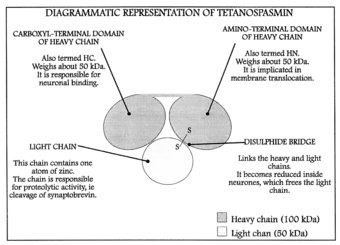

The tetanus toxin protein has a molecular weight of 150 kDa. It is translated from the tetX gene as one protein which is subsequently cleaved into two parts: a 100 kDa heavy or B-chain and a 50 kDa light or A-chain. The chains are connected by a disulfide bond.

- The B-chain binds to disialogangliosides (GD2 and GD1b) on the neuronal membrane and contains a translocation domain which aids the movement of the protein across that membrane and into the neuron.

- The A-chain, an M27-family zinc endopeptidase, attacks the vesicle-associated membrane protein (VAMP).

Once the vesicle is in the inhibitory interneuron, its translocation is mediated by pH and temperature, specifically a low or acidic pH in the vesicle and standard physiological temperatures.[13][14] Once the toxin has been translocated into the cytosol, chemical reduction of the disulfide bond to separate thiols occurs, mainly by the enzyme NADPH-thioredoxin reductase-thioredoxin. The light chain is then free to cleave the Gln76-Phe77 bond of synaptobrevin.[15] Cleavage of synaptobrevin affects the stability of the SNARE core by restricting it from entering the low-energy conformation, which is the target for NSF binding.[16] Synaptobrevin is an integral V-SNARE necessary for vesicle fusion to membranes. The final target of TeNT is the cleavage of synaptobrevin and, even in low doses, has the effect of interfering with exocytosis of neurotransmitters from inhibitory interneurons. The blockage of the neurotransmitters γ-aminobutyric acid (GABA) and glycine is the direct cause of the physiological effects that TeNT induces. GABA inhibits motor neurons, so by blocking GABA, tetanus toxin causes violent spastic paralysis.[17] The action of the A-chain also stops the affected neurons from releasing excitatory transmitters,[18] by degrading the protein synaptobrevin 2.[19] The combined consequence is dangerous overactivity in the muscles from the smallest sensory stimuli, as the damping of motor reflexes is inhibited, leading to generalized contractions of the agonist and antagonist musculature, termed a "tetanic spasm".